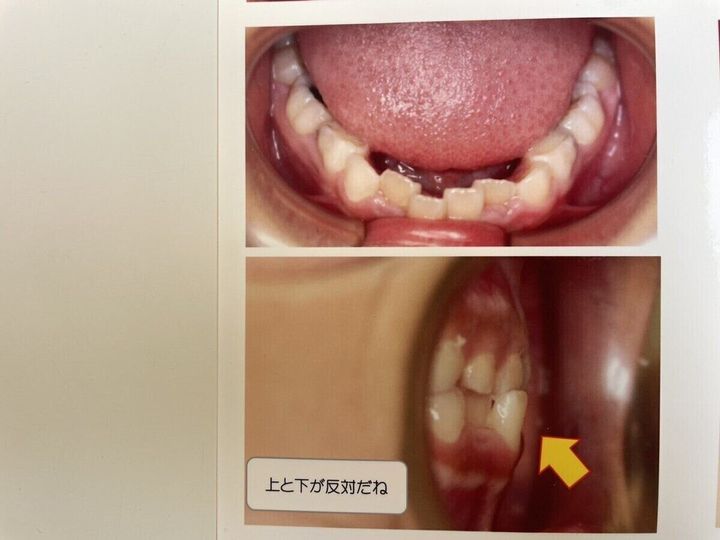

我が家の長女は、産まれたときから”受け口”と呼ばれる「反対咬合」でした。歯を閉じたとき上あごが前に出て、下あごが奥にくるのが通常の噛み合わせですが、名前の通り上あごと下あごが反対なのが、この受け口の特徴です。

矯正前6歳時点

歯列矯正スタート時の写真です。この時点では、まだ噛み合わせが反対で、永久歯は前歯のみですが、ガタガタです。

前歯以外の乳歯の隙間もないため、このままだと、今後生え変わっていく過程で、奥歯もガタガタになってしまいます。

歯列矯正前・1年後

左側が歯列矯正前で、右側が約1年後の経過です。たった1年で下の前歯はキレイに並んでおり、受け口も軽減されています。現在は、受け口はキレイに治っているほか、歯並びも悪くありません。